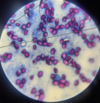

Trypanosoma sp.: Trypomastigotes

Blood smear

Trypanosoma equiperdum: Trypomastigotes

Trypomastigote in the blood

Trypanosoma sp.: Trypomastigote

Fish blood